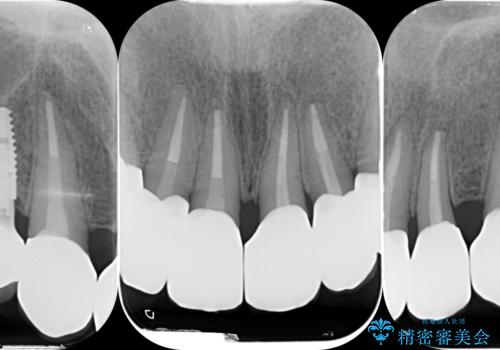

歯周外科を行い歯と歯槽骨・歯肉の関係を是正することで歯ぐきの状態を改善し、将来に亘り安定した歯周環境の維持を期待できるセラミック治療を実践します。

- 95.7万円(ジルコニアクラウン×6・仮歯×6・歯周外科)費用は治療当時の料金となります